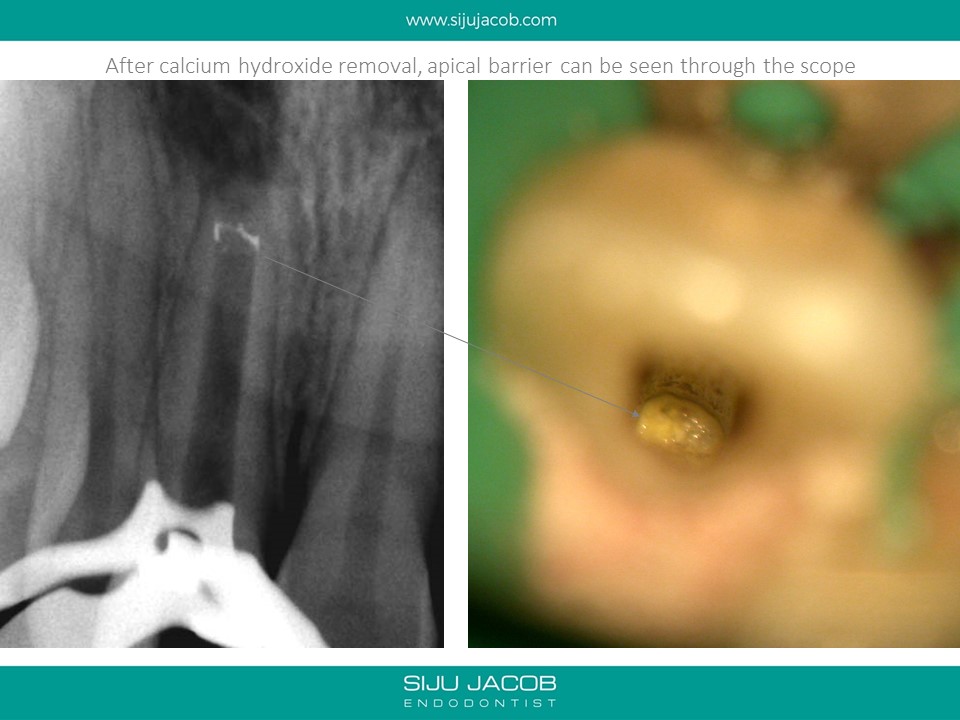

This was one of the first apexification cases i did. I started this case before i purchased a microscope (and I wasn’t using MTA at that time). I packed the canal with a thick Iodoform + Calcium hydroxide (Metapex). By the time the patient came back after a year, I had a microscope and it was fascinating to Microscopically observe the apical barrier that had formed.